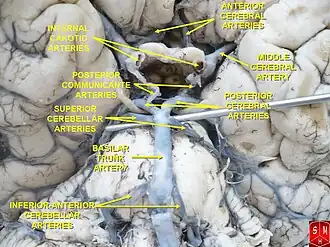

The arteries of the base of the brain. Basilar artery labeled below center. The temporal pole of the cerebrum and the cerebellar hemisphere have been removed on the right side. Inferior aspect (viewed from below). | |

The circle of Willis is a part of the cerebral circulation and is composed of the following arteries:[3]

- Anterior cerebral artery (left and right) at their A1 segments

- Anterior communicating artery

- Internal carotid artery (left and right) at its distal tip (carotid terminus)

- Posterior cerebral artery (left and right) at their P1 segments

- Posterior communicating artery (left and right)

The middle cerebral arteries, supplying the brain, are also considered part of the Circle of Willis [4]

The left and right internal carotid arteries arise from the left and right common carotid arteries.

The posterior communicating artery is given off as a branch of the internal carotid artery just before it divides into its terminal branches - the anterior and middle cerebral arteries. The anterior cerebral artery forms the anterolateral portion of the circle of Willis, while the middle cerebral artery does not contribute to the circle.

The right and left posterior cerebral arteries arise from the basilar artery, which is formed by the left and right vertebral arteries. The vertebral arteries arise from the subclavian arteries.

The anterior communicating artery connects the two anterior cerebral arteries and could be said to arise from either the left or right side.